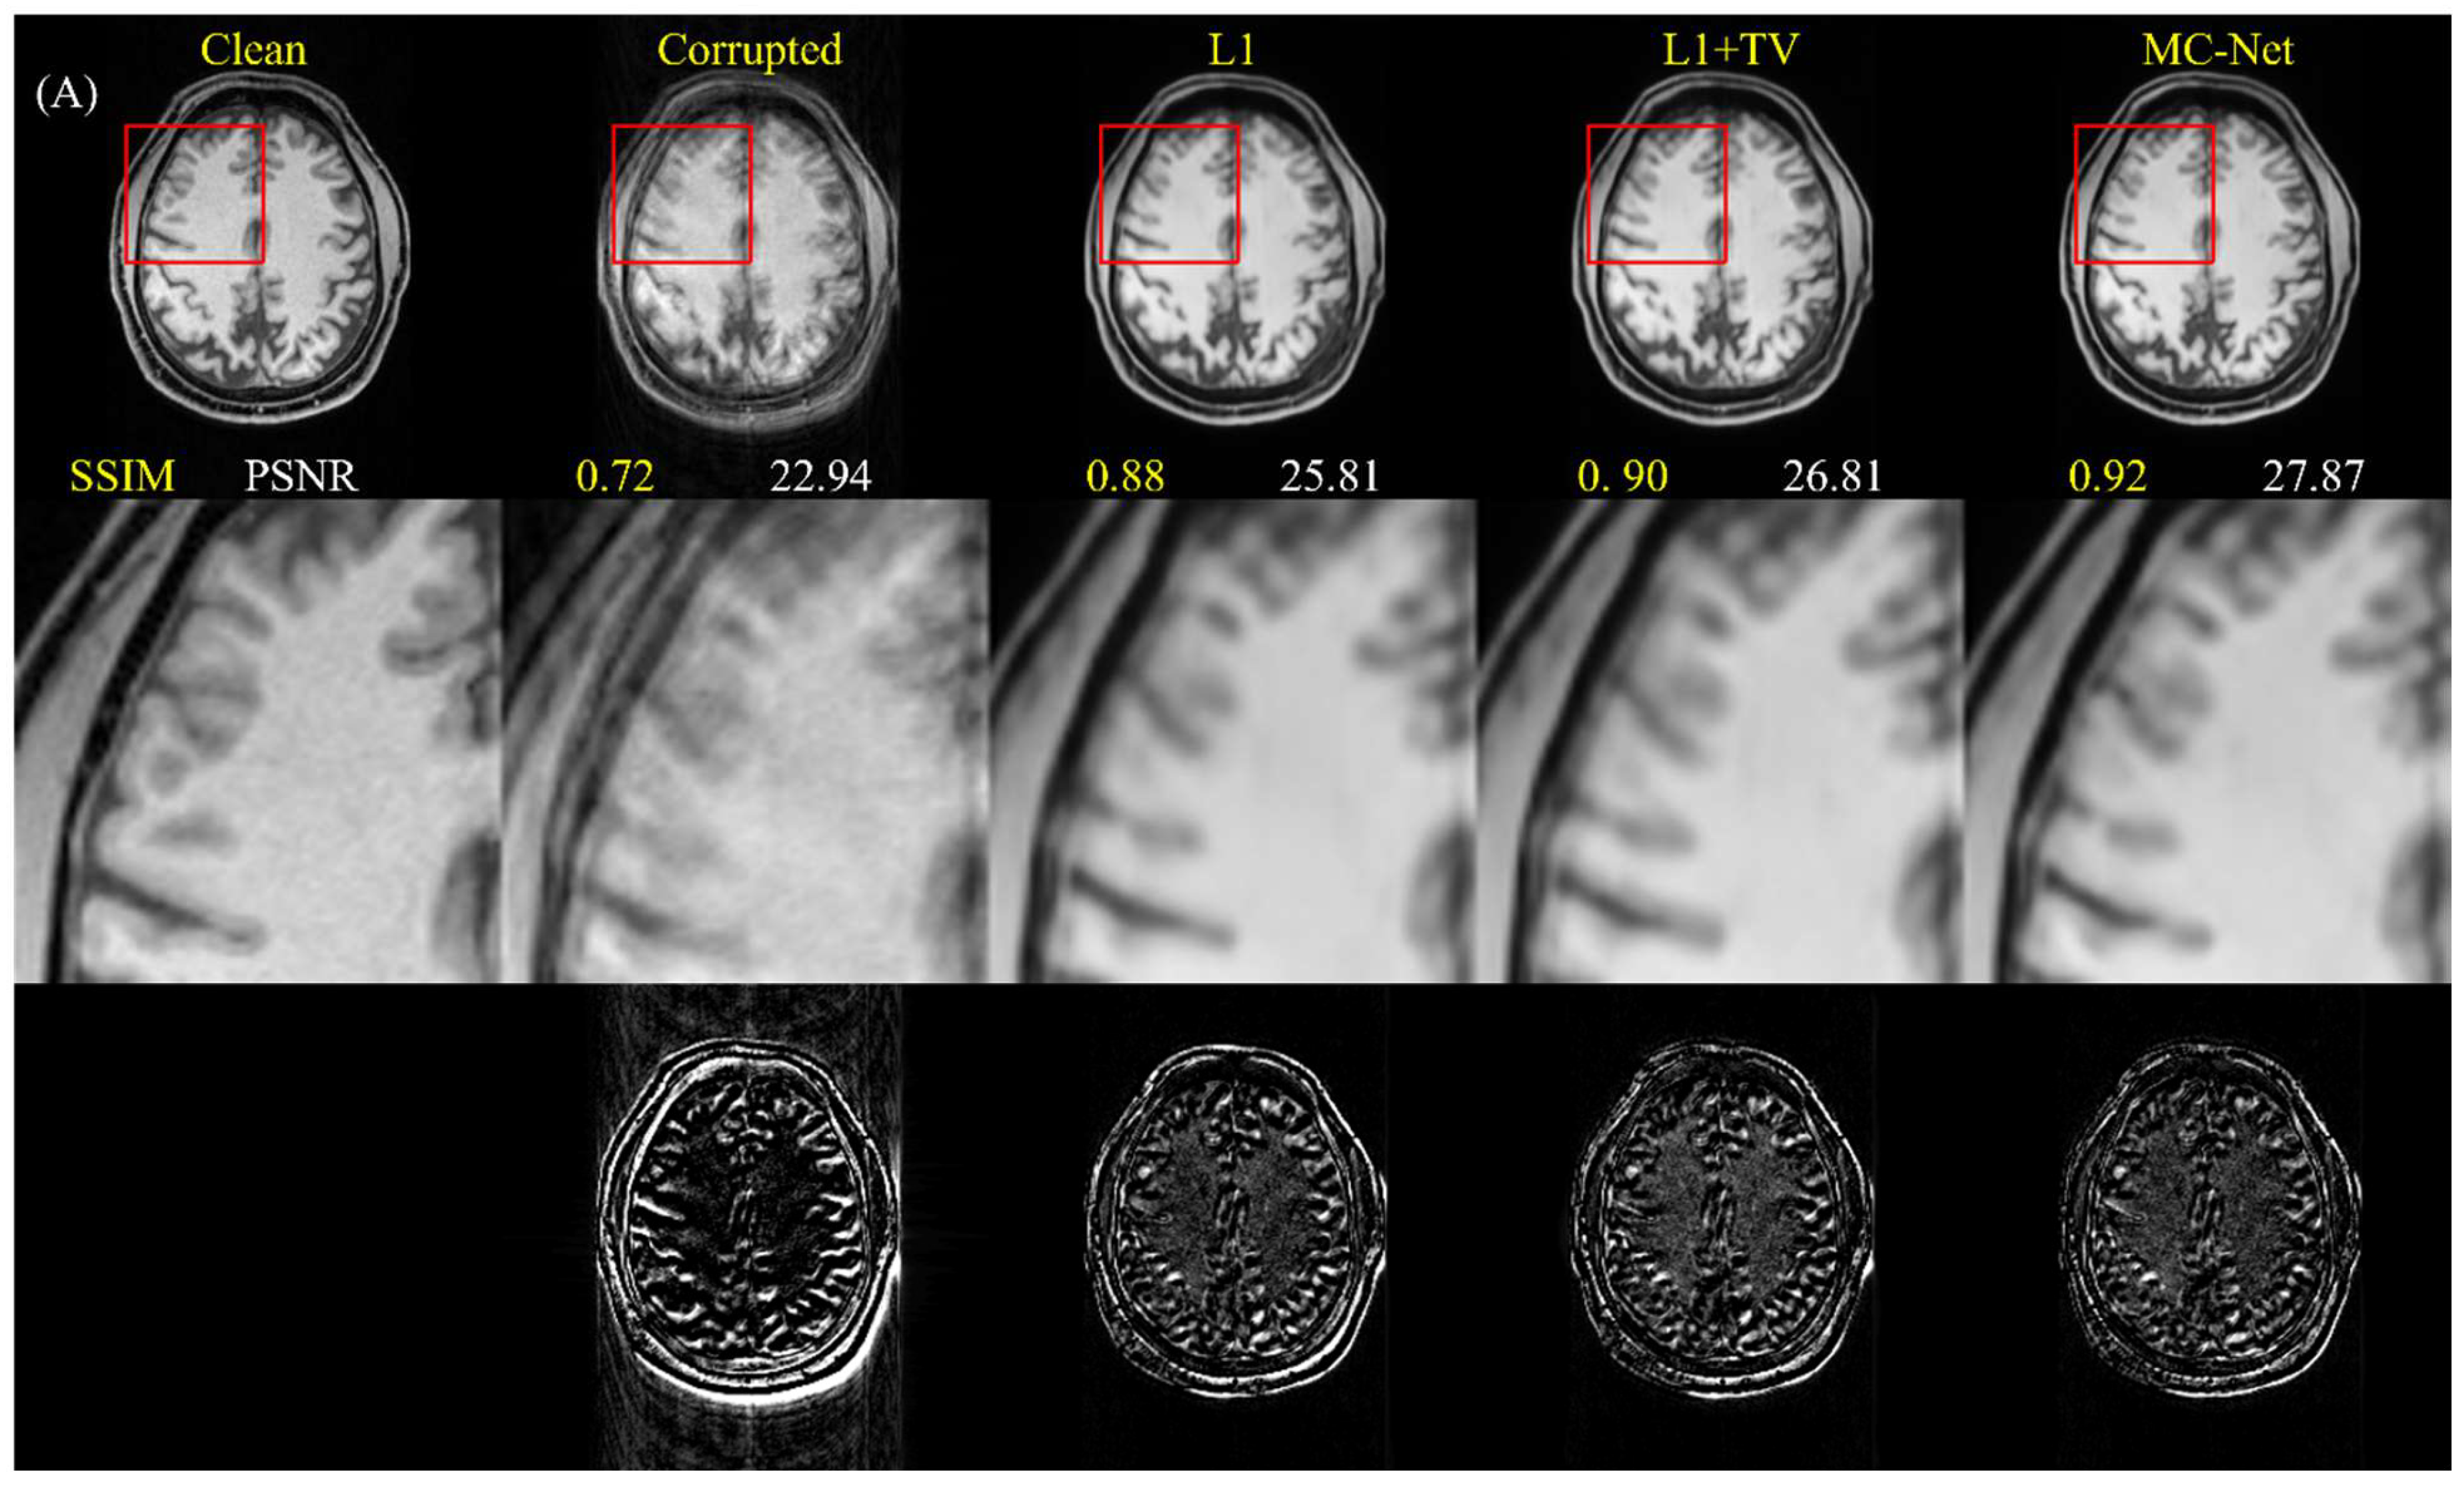

5.1. Advantages of Two-Stage Training and Multiple-Loss Function